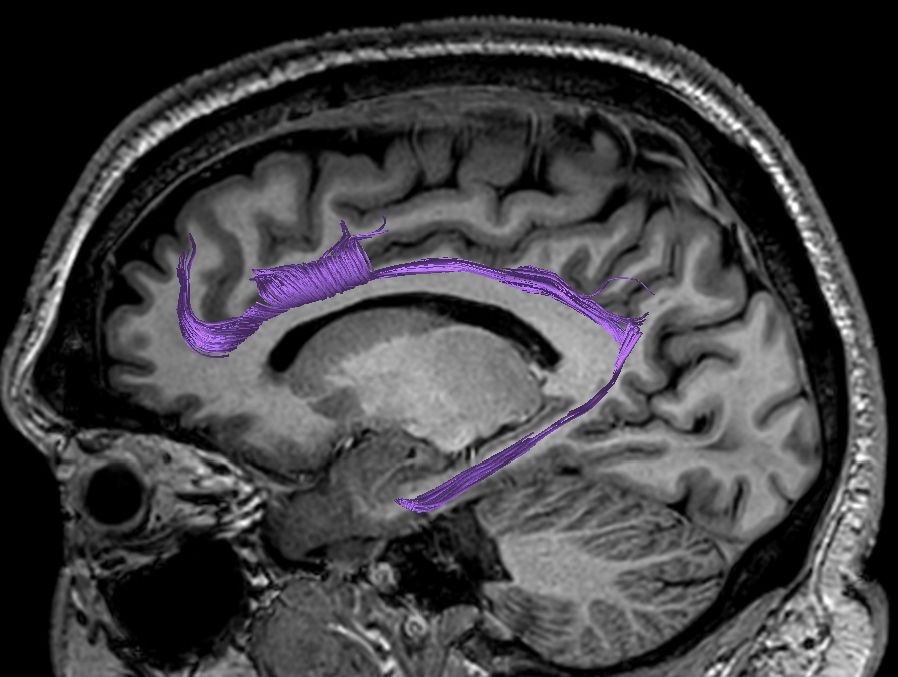

Cingulum. Part of the limbic system, surrounds the corpus callosum medial to other associative and projection fibers. At the level of the splenium an narrow extension of white-matter tract through the parahippocampal gyrus extends to the amygdala.